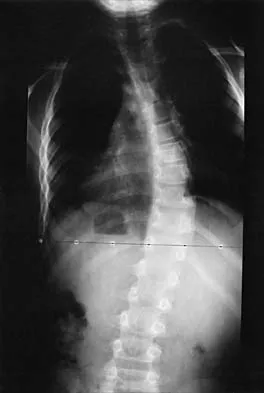

A 28-year-old man sustained a fracture-dislocation of T8 in a motor vehicle accident 1 week ago. The injury resulted in complete paraplegia. Management should consist of

With a complete injury in the thoracic spinal cord, the likelihood of neurologic recovery is small. If possible, treatment should be planned to allow rapid mobilization and rehabilitation without the use of braces and their associated skin problems. The use of long segment fixation provides for rapid mobilization without having to use braces postoperatively. The use of steroid protocol is controversial and should be considered only if it can be started within 8 hours of the injury. Laminectomy is contraindicated because it will increase instability.